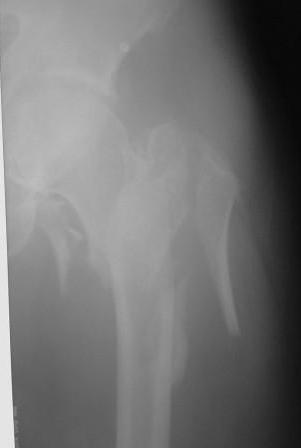

[Ortho] Чрезвертельный перелом бедра

По нашему мнению линия перелома проходит вверху через латеральный отдел шейки бедра, вертельная область состоит из нескольких фрагментов. В таких условиях применить DHS или дистальную бедренную пластину LCP представляется нам сомнительным. Закрытый остеосинтез проксимальным гамма-гвоздем или PFNa невозможен т.к. нет ЭОПа.

Возможно открытый остеосинтез гвоздем PFNa?

Прилагаю Р-ы на вытяжении.